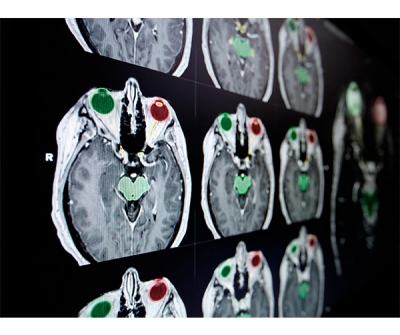

С годами разработка аппаратных систем стала критически важной для портфолио Brainlab. Современное оборудование расширяет возможности лечения, облегчает и эффективно реализует инновации программного обеспечения Brainlab во многих областях: онкология, в частности, радиотерапия и радиохирургия; хирургия под визуальным контролем, в частности, краниомаксиллофациальная (CMF), ЛОР, ортопедия, позвоночник, травмы и нейрохирургия; интраоперационная визуализация; Интегрированные решения для операционных, а также обмен изображениями и улучшение качества изображений. Стремясь к повышению доступности и единообразия лечения, Brainlab фокусируется на повышении выживаемости пациентов с раком, разрабатывая новые малоинвазивные методы лечения опухолей головного мозга и других органов, а также повышая комфорт пациентов во время лечения. С запуском Brainlab.org компания стремится сделать медицинские технологии более понятными и доступными для пациентов и лиц, осуществляющих уход, по всему миру.